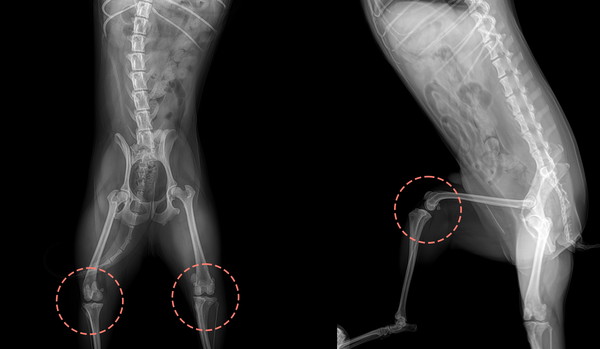

동물병원 방문 시 반려견의 다리와 관절 움직임을 면밀히 검사할 것입니다. 수의사는 슬개골을 만져보고 안정성을 평가하여 탈구 정도를 진단하는 데 도움을 줄 것입니다.

진단 검사

경우에 따라 엑스레이 또는 기타 영상 검사가 권장될 수 있습니다. 이러한 이미지는 반려견의 무릎 관절을 자세히 볼 수 있어 수의사가 반려동물의 필요에 맞는 치료 계획을 세우는 데 도움이 됩니다.